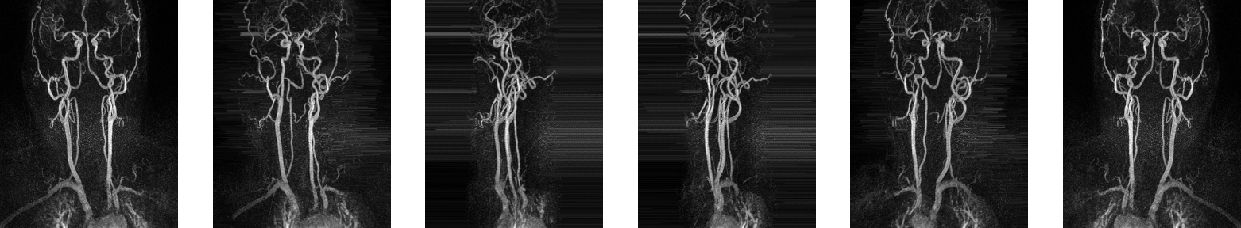

As mentioned in the introduction, the main idea is to include projection layers from different directions. Due to the high sparsity and the orientation of the vessels in our application, maximum intensity projection (MIP) as projection technique seems to be an appropriate choice (Fig. 2).

Refer to caption

Figure 2: MIP images of a 3D MRA scan with directions θ{k×36k=0,,5}𝜃conditional-set𝑘superscript36𝑘05\theta\in\{k\times 36^{\circ}\mid k=0,\ldots,5\}.